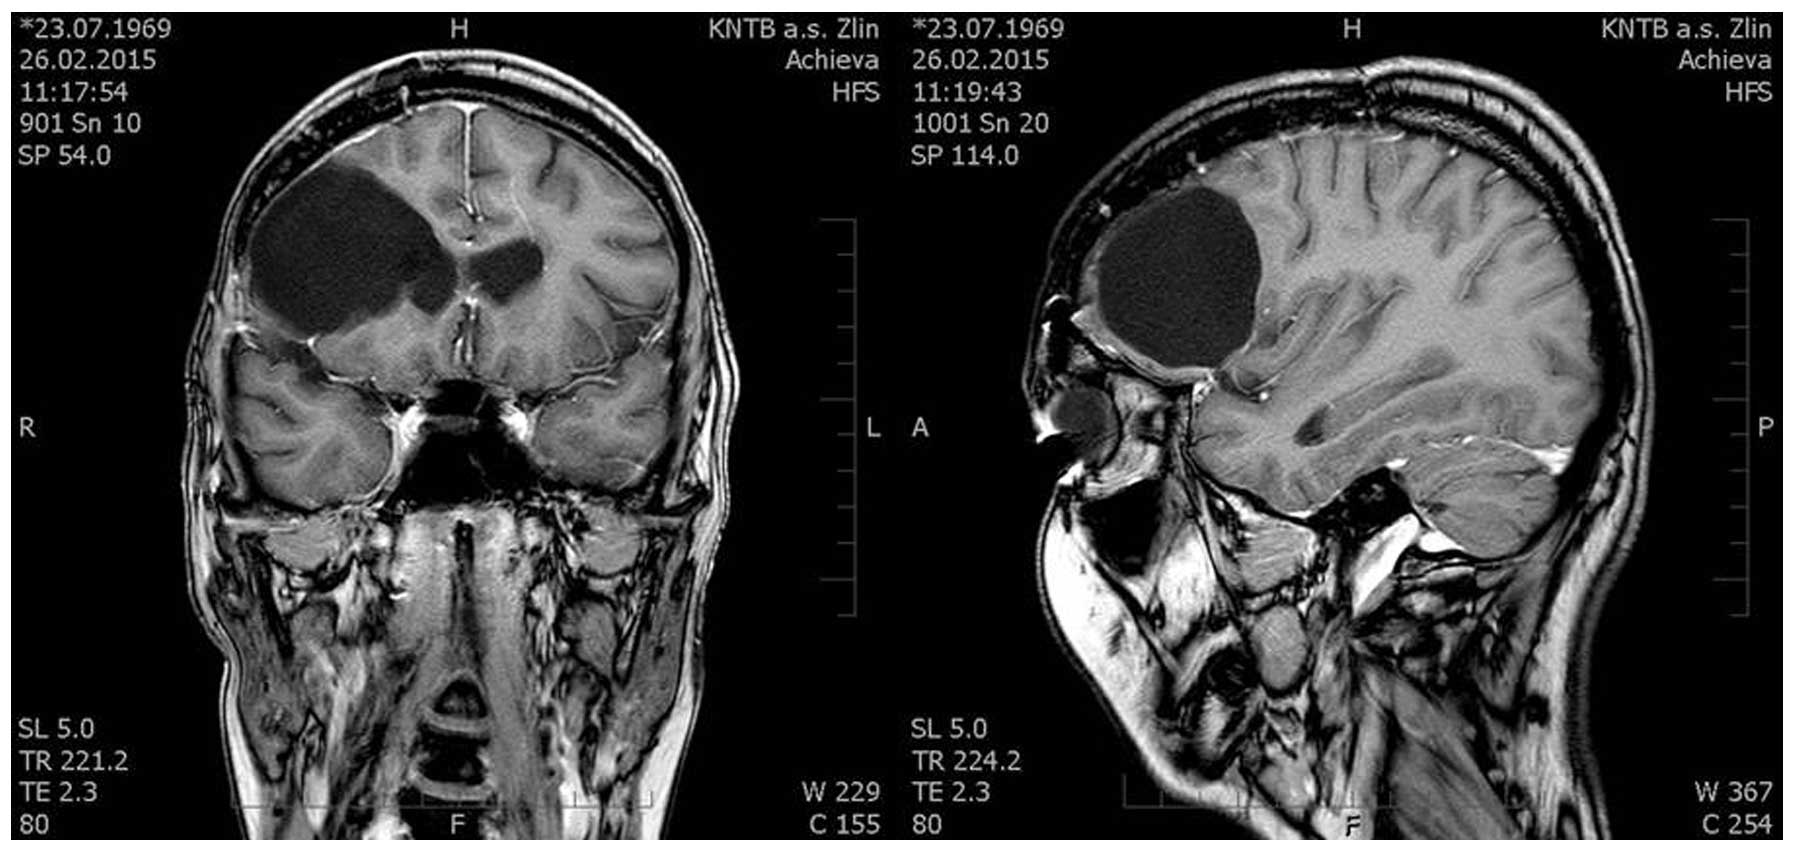

A 44-year-old female patient was examined in the Department of Neurosurgery (Third Faculty of Medicine, Charles University in Prague and University Hospital Kralovske Vinohrady in Prague, Prague, Czech Republic) for headaches that were prominent for 2 months. Headaches were of an increasing intensity and a magnetic resonance imaging (MRI) scan (Figs. 1 and 2) showed a large expansive process in the right frontal lobe (81×70×76 mm), with the pressure on midline brain structures and compression of the ventricular system. The MRI scan indicated a glioma. Neurological examination revealed light left-sided hemiparesis.

Figure 1.

Preoperative magnetic resonance imaging axial scan (high- and area low-grade areas).

Figure 2.

Preoperative magnetic resonance imaging coronal scan (high- and area low-grade areas).

Figure 3.

Postoperative magnetic resonance imaging coronar and sagital scan (high- and area low-grade areas).